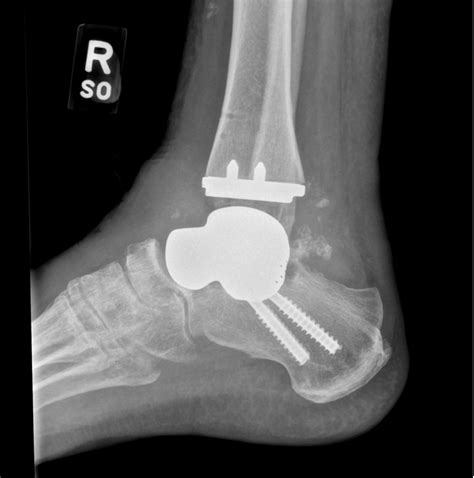

The primary goal of fusing ankle bones is to alleviate pain by stopping the grinding of damaged cartilage surfaces within the ankle joint. Over time, wear and tear, trauma, or underlying conditions like rheumatoid arthritis can cause the protective cartilage to deteriorate, leading to bone-on-bone contact. During the procedure, the surgeon removes the remaining damaged cartilage from the joint surfaces and secures the bones together using hardware like metal screws, plates, or rods. Over several months, the body’s natural healing process bridges these bones with new bone tissue, creating a solid, permanent unit.

• Failed Joint Replacement: In cases where an ankle replacement has worn out or suffered complications, fusion often serves as a reliable "salvage" procedure.

Modern surgical techniques, including minimally invasive arthroscopic fusion, have made the procedure safer and more accessible than ever. By utilizing smaller incisions, surgeons can achieve the same solid fusion as traditional open surgery while often reducing the risk of complications such as wound healing issues or infections. Choosing the right surgeon and adhering strictly to the post-operative recovery plan are the two most important factors in achieving a successful long-term outcome.